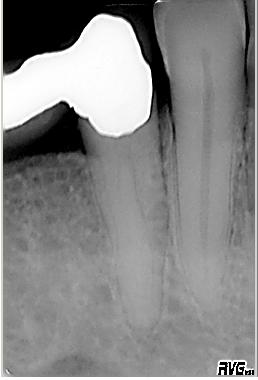

Röntgenologischer Ausgangsbefund

Röntgenologischer Ausgangsbefund im Dez. 2001 mit einem Langzeitprovisorium. Zwei Kanalsysteme sind zu erkennen

Messaufnahme

Erste orientierende Messaufnahme des bucc. Kanales nach vorgängig durchgeführter Endometrie

WF Kontrollaufnahme

WF Kontrollaufnahme im Dez. 2001. WF in lateraler Kondensation mit genormter Guttapercha und AH 26. Der linguale Kanal war nicht weiter erschließbar

WF Kontrolle

WF Kontrolle ein Jahr später im Dez. 2002